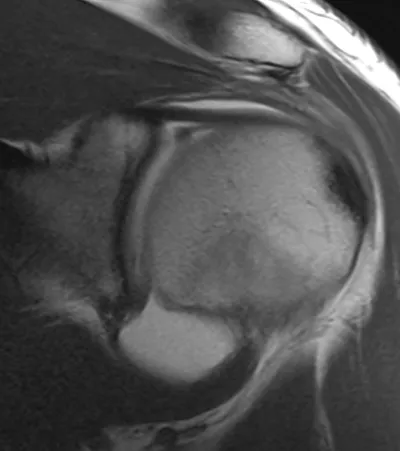

SLAP tear (Superior Labrum Anterior and Posterior)

Arthrogram

4/11/2026